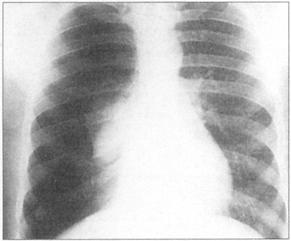

①周围性发绀及周围静脉扩张是由COPD引起的CO2潴留的主要特征(图76)。②脊柱侧后凸常预示患者有某种呼吸系统疾病的倾向(图77)。③结核的X线表现(图78)。④肺尖部结核所致的纤维化多引起上胸部变平(图79),由于脊柱常受累,故多有成角。⑤支气管肺癌(图80)。⑥大叶肺炎患者常伴发单纯疱疹病毒感染(图81、图82)。⑦如肺组织萎陷(如气胸),则胸片上无法看到肺纹理(图83)。

图81 大叶性肺炎,这个患者有右肺实变

图82 单纯疱疹病毒感染在大叶性肺炎患者常见